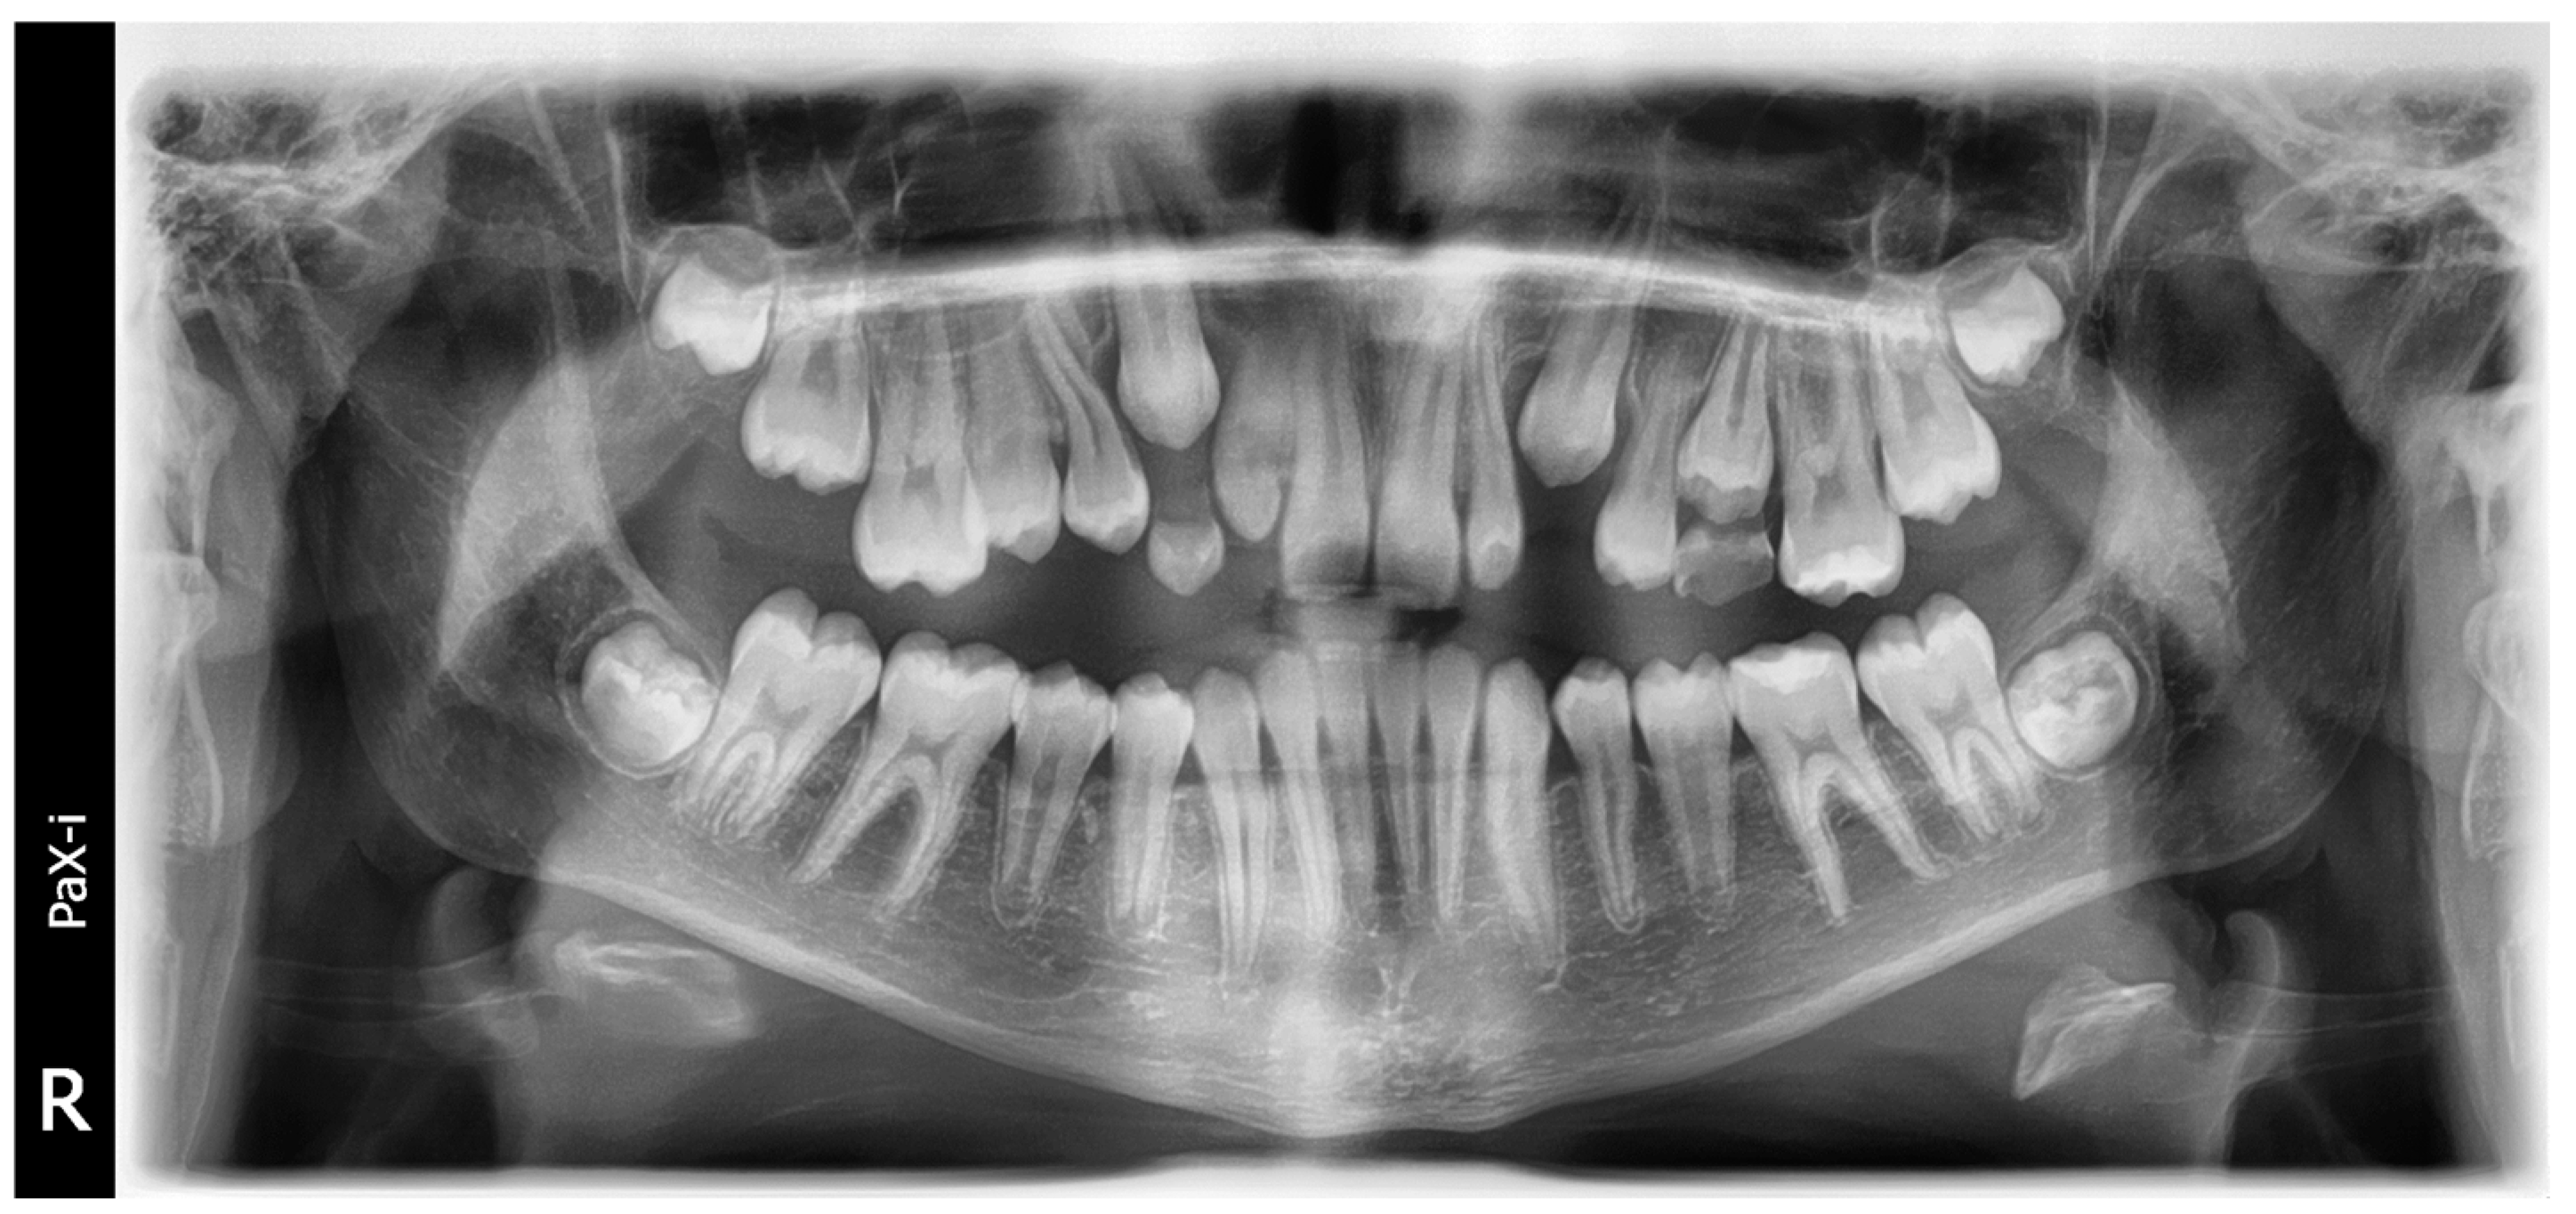

2.3.1. Reading Images

2.3.2. Preprocessing Step